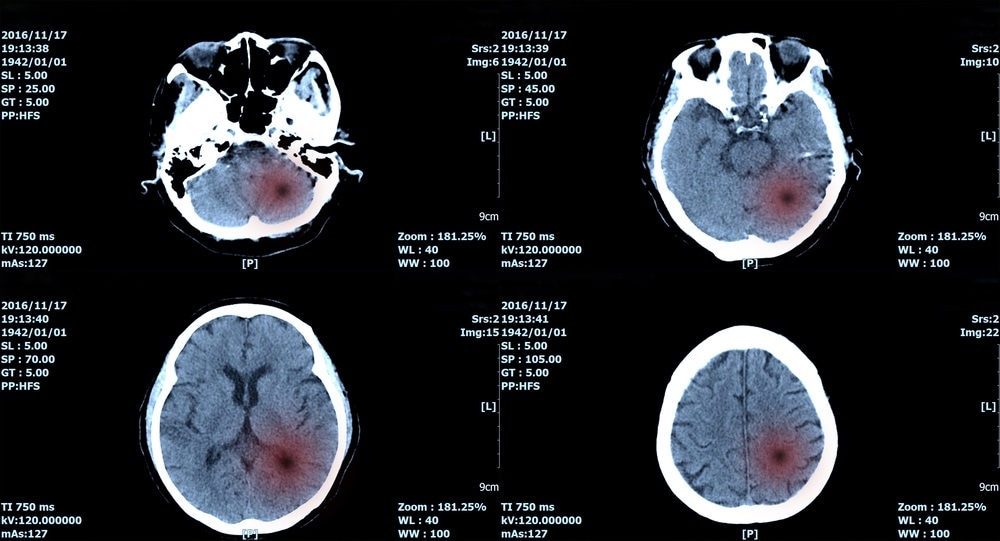

Image Credit: create jobs 51 / Shutterstock.comImage Credit: create jobs 51 / Shutterstock.com